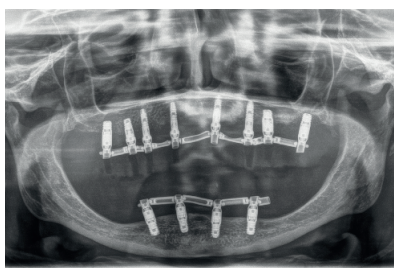

Presentamos el caso de una mujer de 67 años que acude a la consulta para solicitar un tratamiento que mejore la estética y la funcionalidad de las prótesis removibles que porta. En la radiografía panorámica inicial se observan dos implantes en la región anterior mandibular que actualmente no están formando parte de la rehabilitación, que en algún momento sostuvieron una barra para una sobredentadura (Figura 2). En la imagen de sonrisa e intraoral podemos ver la prótesis removible superior e inferior deteriorada y con zonas fracturadas (incisivo central superior derecho) (Figura 3). Al retirar las prótesis podemos observar los implantes con dos tornillos fracturados en su interior (Figura 4).

Una vez finalizada la confección de la prótesis, se coloca en el paciente. En las imágenes podemos observar el resultado clínico final y la radiografía, donde puede verse el ajuste de las estructuras sobre los implantes (Figuras 24-26).

Podemos observar la comparación entre el estado inicial y el resultado final, que satisface los deseos estéticos y funcionales de la paciente y además recupera la dimensión vertical perdida con las prótesis removibles (Figuras 27-30).